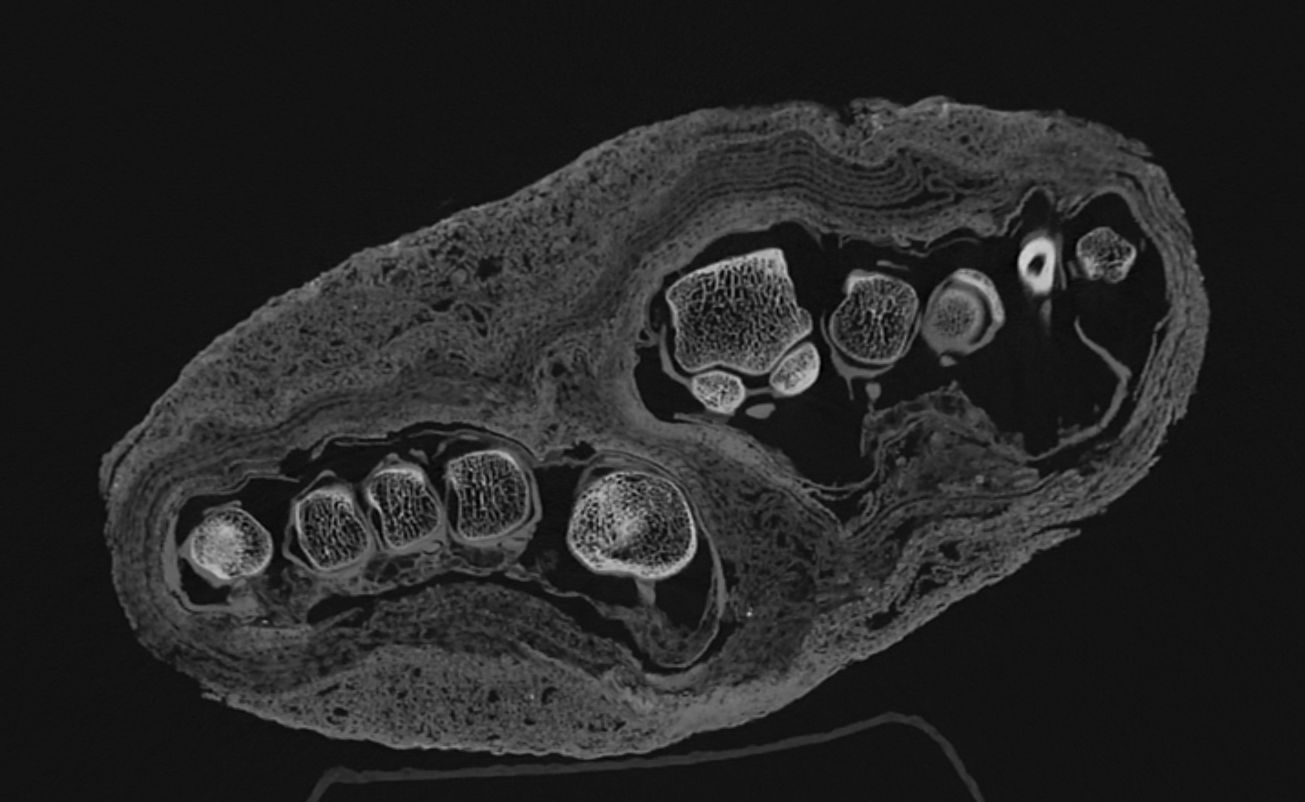

Különösen figyelemre méltó eredményt hozott egy, eddig csak múmiacsomagként értelmezett maradvány vizsgálata. A leletet a múzeumba kerülésekor – képalkotó vizsgálatok hiányában – fejként, később esetleg madármúmiaként határozták meg. Egy korábbi CT-vizsgálat azonban egyértelműen kimutatta, hogy egy felnőtt egyén lábfejéről van szó. A mostani képalkotó elemzés során arra keresik a választ, hogy a textilmaradványokból mennyire következtethetünk a mumifikálási technikára, valamint a mumifikált egyén életkorára, esetleges betegségeire. Az aktuális felvételeken ugyan is jól elkülöníthetők a különböző bandázsrétegek, valamint azok eltérő szerkezeti sajátosságai. Ezek további történeti és technológiai vizsgálatok alapját képezhetik. A maradvány egykor feltehetően egy teljes múmiához tartozott, azonban a test feldarabolásának ideje és oka jelenleg nem ismert.

A második bal alsó végtag vizsgálata során megállapíthatóvá vált, hogy egy fiatal egyén maradványáról lehet szó. A pontos életkor meghatározása jelenleg is folyamatban van, azonban ez az első alkalom, hogy a leletről ilyen jellegű, részletes képalkotó információk állnak rendelkezésre.